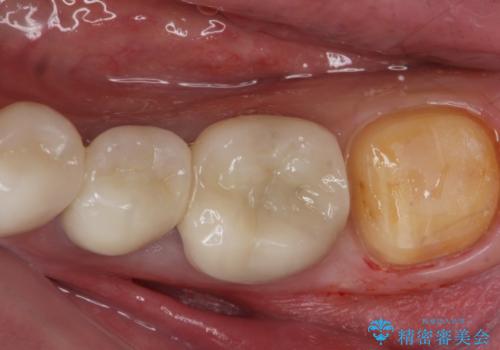

- 過去に治療したゴールドの詰め物が取れて来院。取れたのは2回目だそうです。レントゲンでは適合が良いので再装着可能だったが、

もう取れたくないとの事だったので被せ物のご案内をしました。ゴールドの被せ物の希望だったのでゴールドクラウンでの治療になりました。

適合の良いゴールドクラウンが入りました。

ゴールドは適合が良く、割れる心配もありません。

また、虫歯になるリスクも銀歯と比べて低くなります。